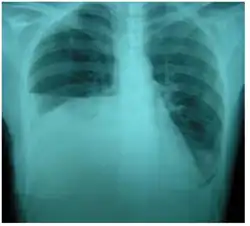

| Right sided pleural effusion caused by urinothorax | |

Urinothorax (pl. urinothoraces) is defined as urine in the fluid-filled cavity that surrounds the lungs.[1] It is usually caused by obstructive uropathy. It is mainly diagnosed by analyzing the pleural fluid. Treatment involves treating the underlying condition, which typically results in resolution of the urinothorax. It is an extremely rare cause of pleural effusion.[2]

The characteristics of people affected by urinothorax are poorly defined. Urological symptoms tend to occur, while the respiratory symptoms are typically nonexistent or mild.[3] Difficulty breathing, occurring in moderate to large pleural effusions, is the most common respiratory symptom.[4] Other symptoms include fever, abdominal pain, chest pain, and reduced urination.[3] It typically occurs within hours of the causative condition.[5]